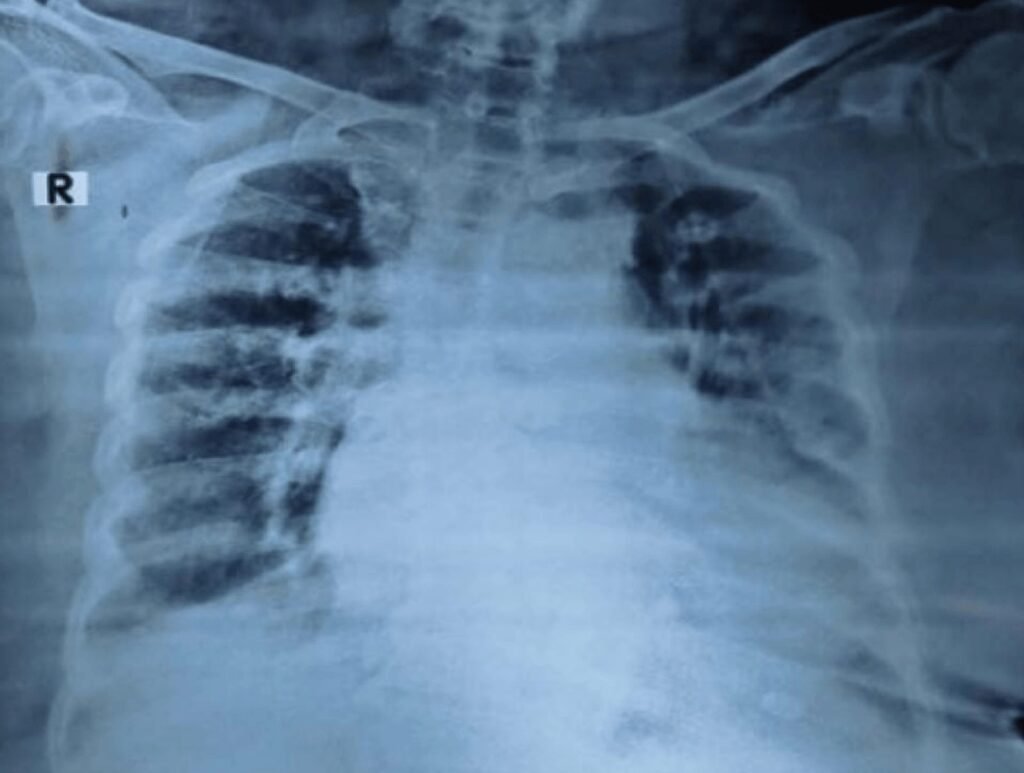

- Elderly Diabetic Female admitted in ICU of AIMS with sudden Palpitations with severe Breathlessness for 4 hours.

- She gave past h/o Breathlessness for 3 years.

- CBC: Hb 10.5 gm, TC, DC and Platelets within normal limits Blood Sugar: 140gm (F), HbA1c 7.5, Serum Creatinine 1.0 gm

- Her ECG and X-ray chest given below:

- Diagnosis

- DCMP with Global Hyperkinesia and LBBB with EF 30% DM, DCMP with Atrial Flutter and Heart Failure.

- Patient was given IV Lasix and, Verapamil 40mg 2 stat and 1 tds, Amiodarone 200 mg bd and Enalapril 2.5 mg od, Dapagliflozin 10 mg od and Metformin 500 mg od